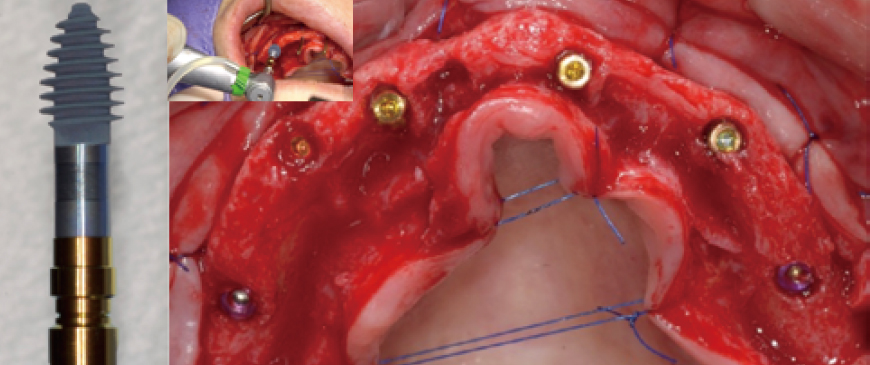

Fig 4

4 straight implants were placed between the two tilted implants. Due to the very thin alveolar ridge in the anterior area, a 3.5mm ARi fixture was chosen.

Fig 5

After drilling with a 3.3mm drill, the ARi fixture provided excellent initial stability. The bone density was D2, and an ARi (2.8) 3.5x9.0(6) fixture was placed to cover the labial defect.

Fig 6

Four ARi implant fixtures were placed. A 5-6mm dehiscence occurred on the labial side, but it was limited to the machined cuff.

Fig 7

To prevent potential visibility through the thin biotype gingiva in the future, a layer of Ossix Volumax (10x40mm) was placed.